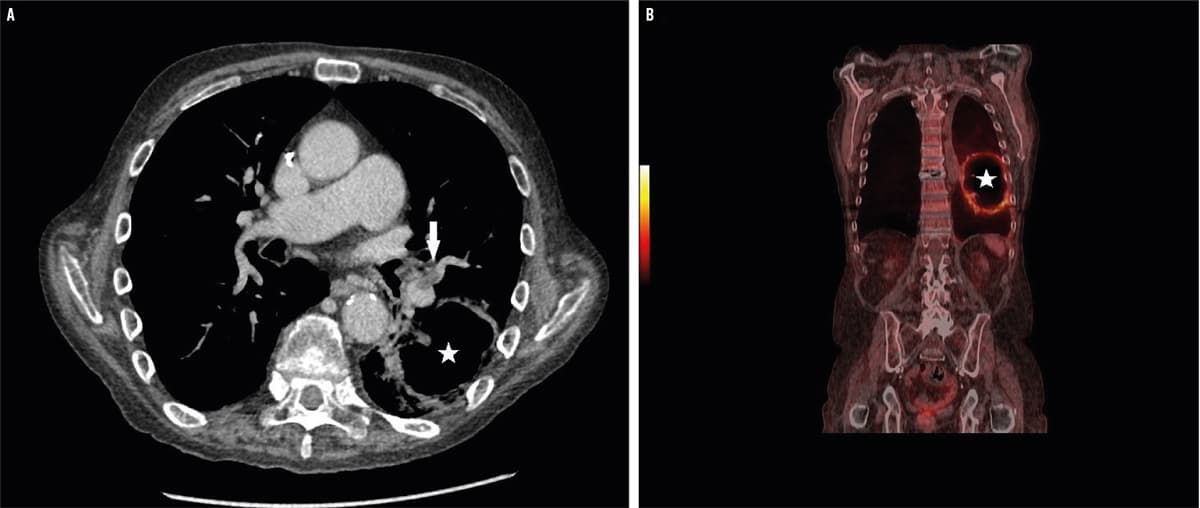

En 60-årig mand blev indlagt med forværring i åndenød gennem en måned, rygsmerter samt et vægttab på 10 kg. Ved indlæggelsen var niveauet af C-reaktivt protein 400 mg/l, og ved en røntgenoptagelse påviste man en 8 x 8 cm stor kavitet i venstre lunge. Dette gav mistanke om en tømt absces, hvilket blev bekræftet ved en CT, hvor man i tillæg påviste flere lungeembolier (LE) bilateralt (A, pilen viser LE, stjernen viser absces). Abscessen var ikke synlig på et røntgenbillede taget fire dage forinden. En supplerende PET/CT viste opladning af abscessens kapsel og afkræftede malignitet (B, stjernen viser absces). Bakteriel agens blev ikke identificeret, og patienten bedredes på behandling med bredspektret antibiotika i seks uger samt warfarin i seks måneder.

Det er estimeret, at 10-31% af patienter med LE vil udvikle lungeinfarkt [1, 2], og 4-7% af infarkterne vil være kaviterende [3]. Disponerende faktorer er bl.a. hjertesvigt, KOL og infektion [4]. Pga. multiple LE og kun én absces formodes et aseptisk infarkt at være grobund for den efterfølgende abscesdannelse hos denne patient. Sammenhængen er velkendt, men sjælden og bør primært haves in mente hos disponerede personer og ved behandlingssvigt.